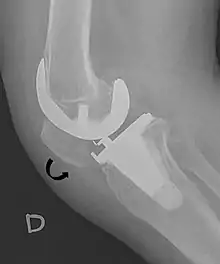

The Insall-Salvati ratio helps to indicate patella baja on lateral X-rays, and is calculated as the patellar tendon length divided by the patellar bone length. An Insall-Salvati ratio of < 0.8 indicates patella baja.[6]

- ↑ Melloni, Pietro; Veintemillas, Maite; Marin, Anna; Valls, Rafael (2013). "Imaging Patellar Complications After Knee Arthroplasty". Arthroplasty - Update. doi:10.5772/53666. ISBN 978-953-51-0995-2. (CC-BY-3.0)

- 1 2 Douglas Dennis (2017-02-25). "TKA in Patella Baja (Infera)". Orthobullets. Retrieved 2019-02-08.